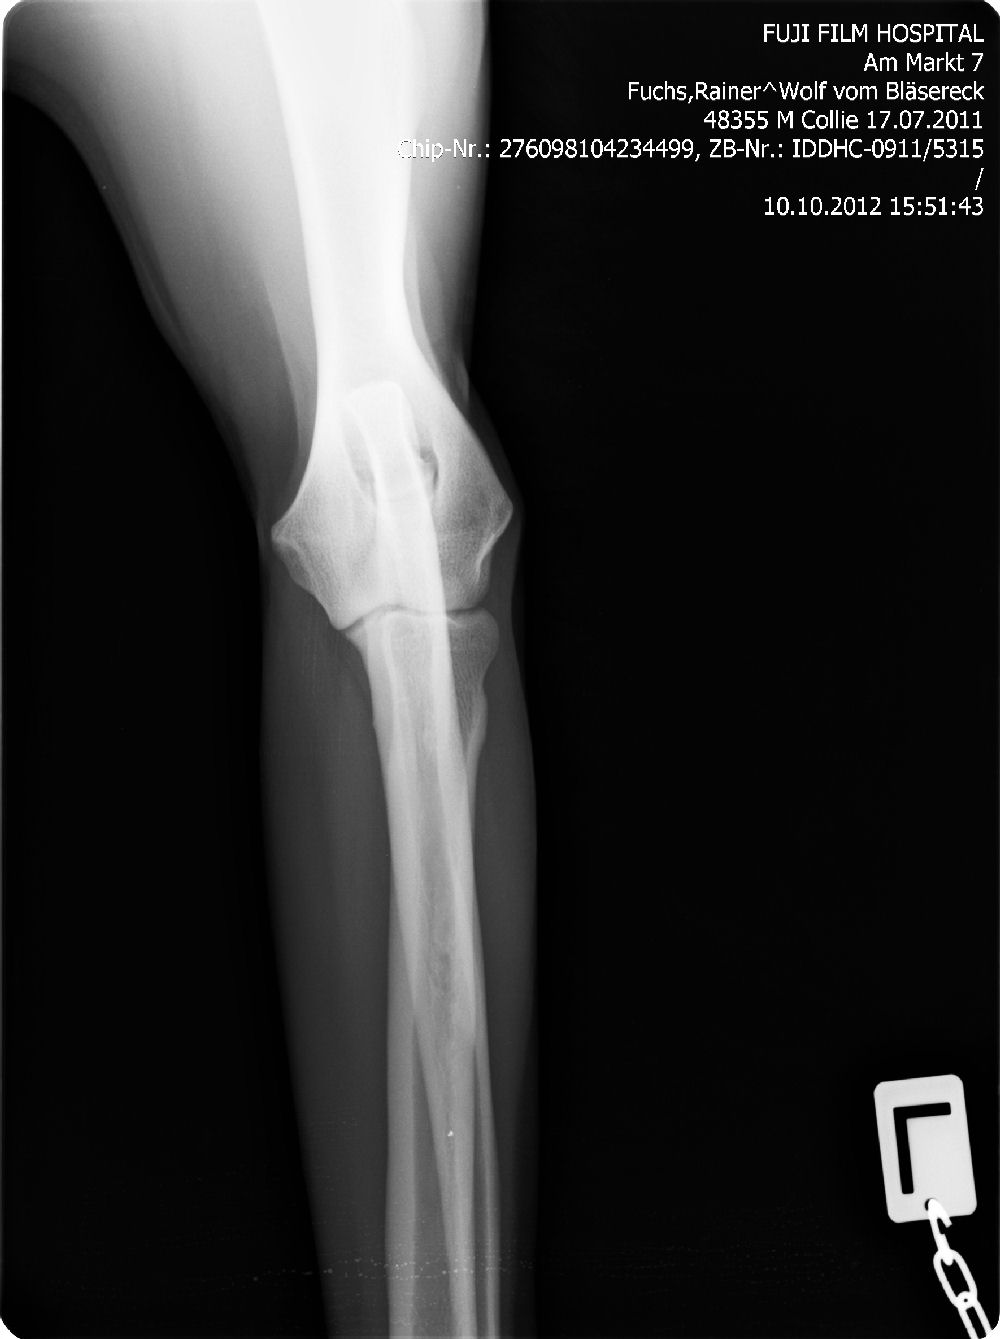

Ab dem Jahr 2008 wird nur noch Digitales Röntgen durchgeführt, da wir auch hier wieder führend und transparent sind, zeigen wir gern die Röntgenbilder ! Bei Züchtern, die dies nicht tun, haben Sie weniger Sicherheit !